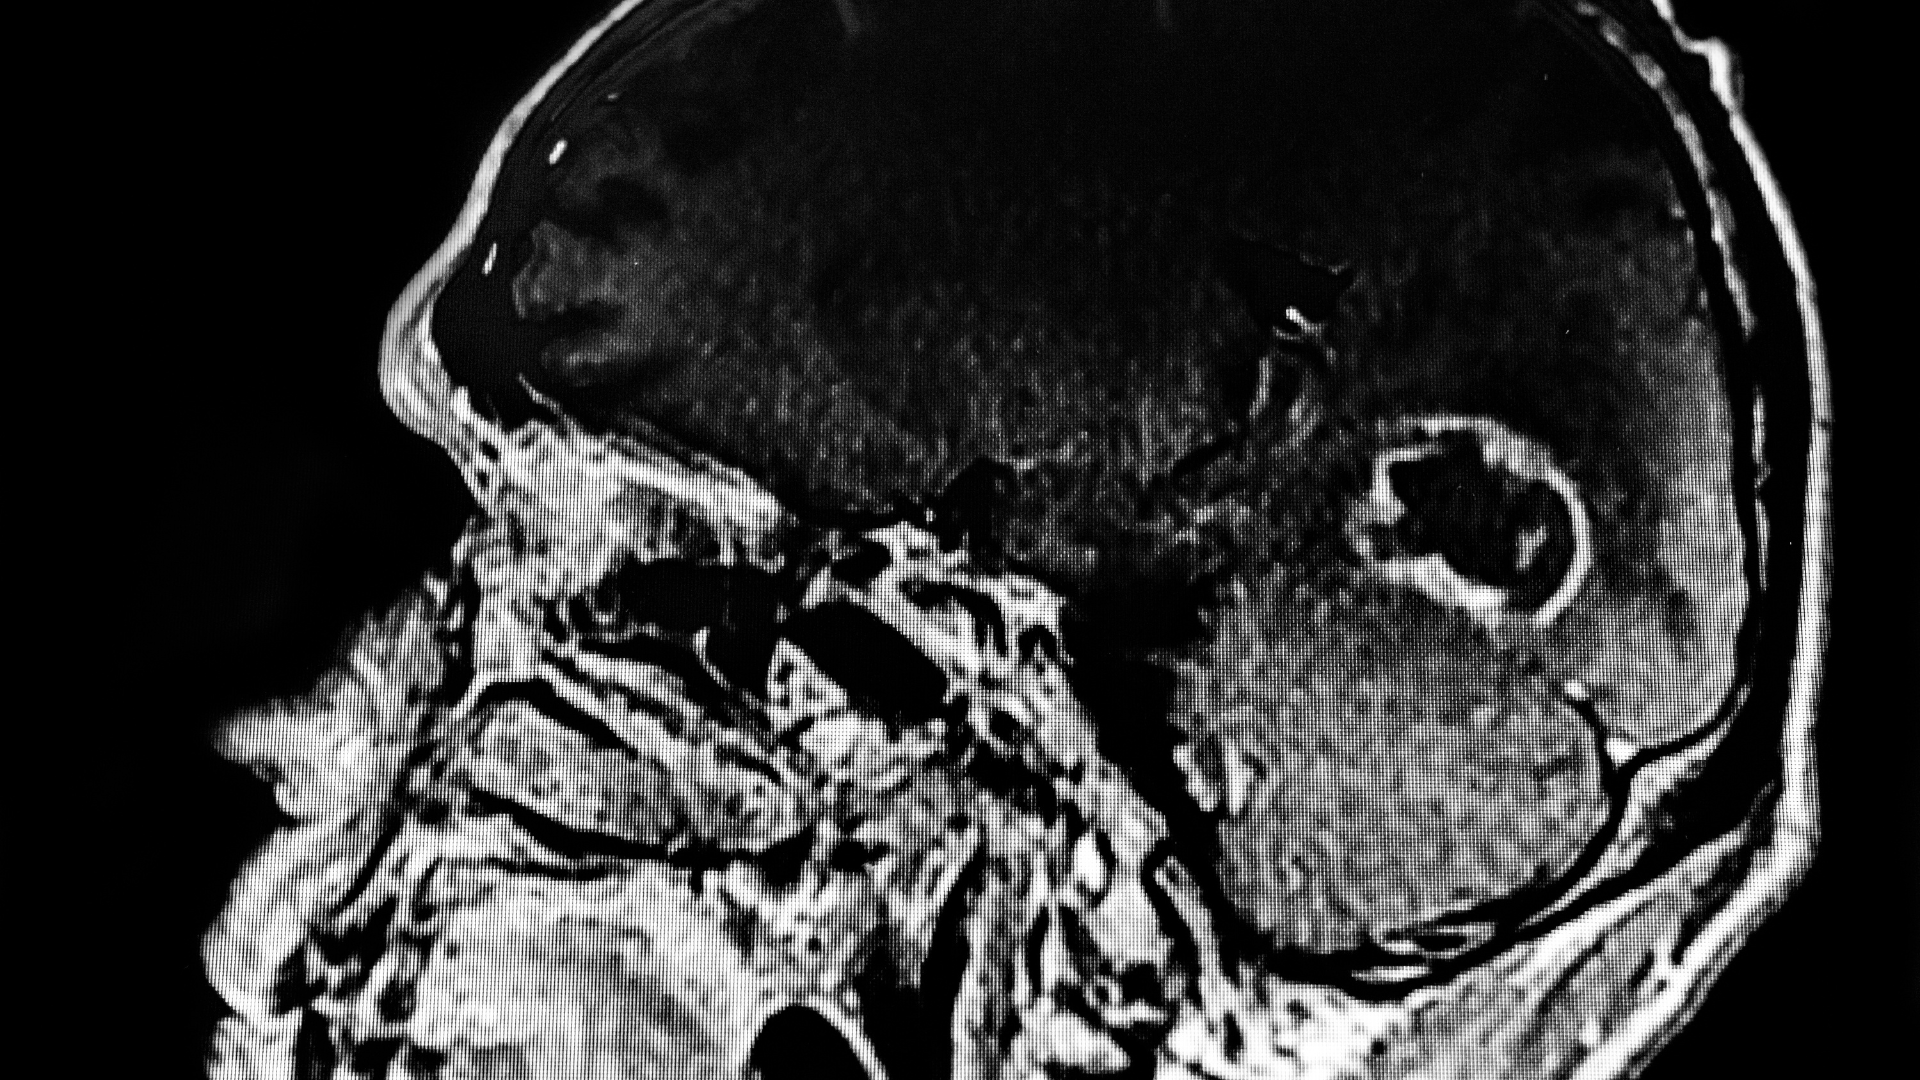

In addition to these short-term effects, there are also long-term symptoms which can really cause problems for the sufferer. It can lead to serious illness and it can spread to the brain in a short timescale. If this parasite does reach the brain, it can cause blindness and a whole range of other issues in those with a vulnerable immune system. There is even the risk of toxoplasmosis gondii contamination leading to brain cancer in some cases, so compensation is essential.